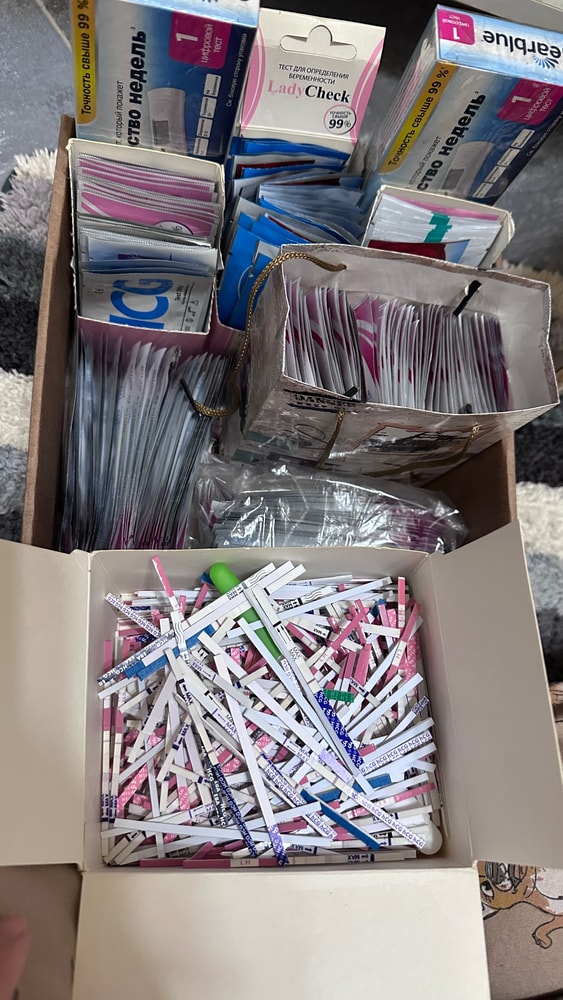

Собрала тесты с цикла в коробку, как всегда😩

Вышла из дисперсии очередной неудачи…заказала тесты, уже в пути…ведь тестов много не бывает, уж я то знаю, спустя столько л